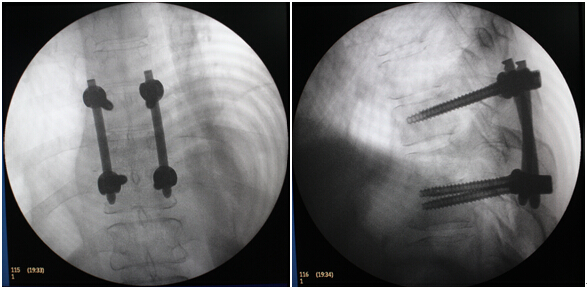

2.后路经皮椎弓螺钉内固定。

此次手术秉承微创理念、创新意识,将经皮脊柱内镜技术成功应用于脊柱结核的治疗,为甘肃省首例。手术的顺利完成,使我院在脊柱微创领域的医疗技术进一步提高。